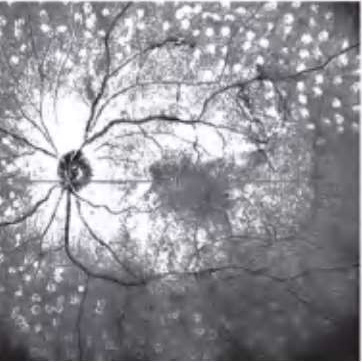

图2-2-1 抗VEGF及PRP治疗后玻璃体后脱离范围显著扩大的PDR案例

A.PDR合并玻璃体视网膜牵拉引发的相关DME,既往已行PRP,行4次抗VEGF药物治疗后,黄斑区玻璃体后界膜与视网膜分离(白色箭头所示),玻璃体视网膜牵拉解除,黄斑水肿较前明显好转。B.PDR合并玻璃体视网膜牵拉性相关DME,在行3次视网膜激光光凝治疗后,黄斑区玻璃体后界膜与视网膜分离(白色箭头所示),玻璃体视网膜牵拉缓解,黄斑水肿较前好转。